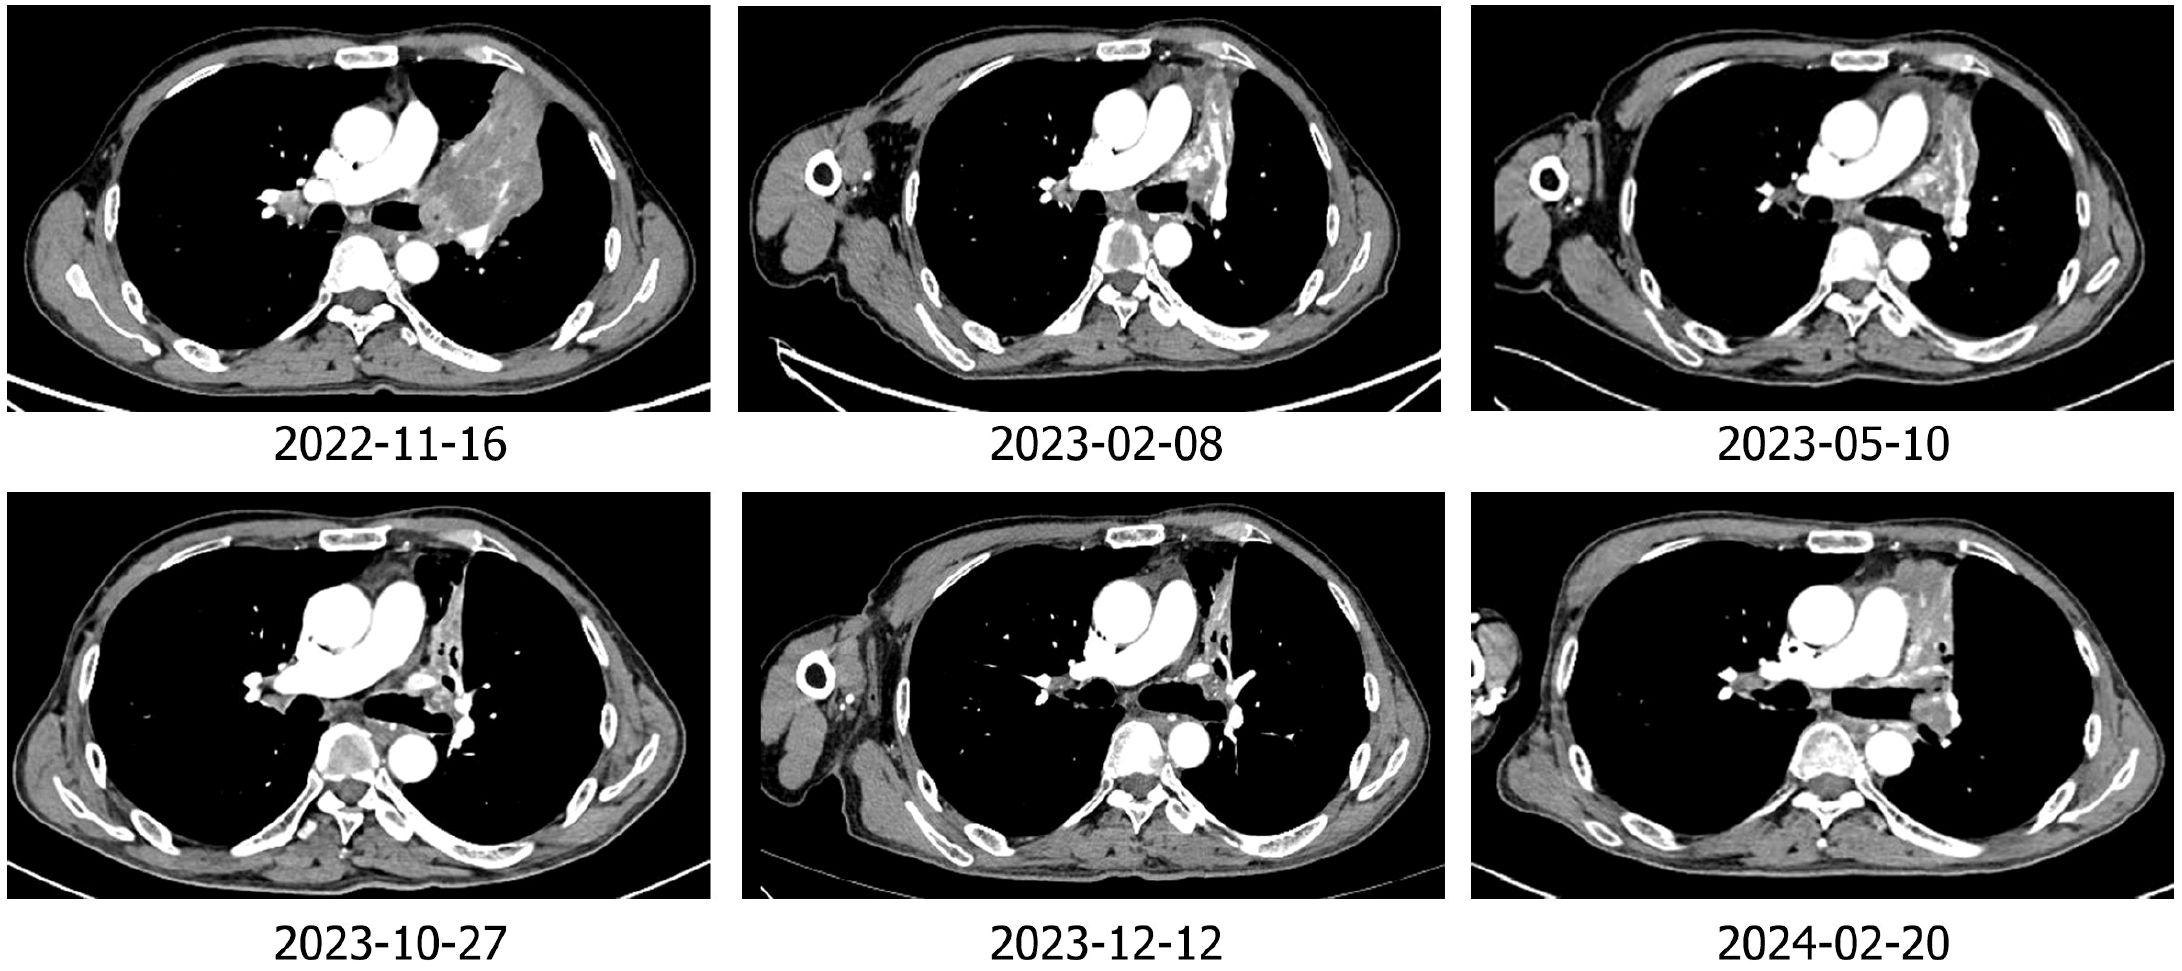

The patient was Li XX, 58 years old, male, smoking index 500. In 2022-02, the patient was treated for “cough”. Chest CT revealed a soft tissue shadow in the left hilum of the lung, multiple enlarged lymph nodes in the mediastinum and hilum of the lung, and nodules in the outer basal segment of the lower lobe of the right lung. Fibrobronchoscopy revealed a new protuberant lesion that was located in the opening of the upper left lobe, blocking the lumen. Forceps biopsy was performed. Pathological analysis of the specimen revealed large-cell neuroendocrine carcinoma of the upper left lobe. The immunohistochemical results were as follows: Syn (+), CD56 + (weak), CgA (-), CK (focal point +), CK5/6 (-), Ki -67 (+ 80%), NapsinA (-), P40 (-), and vera.ttf (+) - 1 (Figure 1). The patient was diagnosed with left lung large-cell neuroendocrine carcinoma, stage cT1N2M1aIVA (right lung). From 2022-2-18 to 2022-7-17, he received chemotherapy consisting of the EP regimen (etoposide 0.-4+ carboplatin 400 mg/d1) for 6 cycles, and the best efficacy evaluation was a PR. A review of a chest CT image taken on 2022-08-11 revealed a space-occupying lesion of the left upper hilum, which measured approximately 4.3*3.6 cm in size and was significantly larger than before. Multiple enlarged lymph nodes were observed in the mediastinum and hilum. The revised diagnosis after a complete examination was as follows: stage cT4N3M1aIVA left lung large-cell neuroendocrine carcinoma (right lung). In 2022-09, the patient was enrolled in the “randomized, open, multicentre phase III clinical study to evaluate the efficacy and safety of sofratinib combined with toripalimab versus FOLFIRI as second-line treatment for advanced neuroendocrine carcinoma”, and he was randomized to receive chemotherapy alone. Chemotherapy with the FOLFIRI regimen was performed for 4 cycles: 2022-09-09, 2022-09-24, 2022-10-09 and 2022-10-25. During chemotherapy, the patient’s gastrointestinal reaction was grade III, with no obvious bone marrow suppression. PD was evaluated after 4 cycles (target lesion: left pulmonary lesion 7.5 cm→9.3 cm), and consequently, a clinical trial was conducted. The patient was treated with sofratinib combined with toripalimab in 2022-11-18, 2022-12-30, and 2023-01-16. After 3 cycles of treatment, the mass in the upper lobe of the left lung was smaller than before (9.3 cm→7.9 cm), and the efficacy was evaluated as SD (15%↓). During the treatment period, the patient experienced no adverse events such as rash, bleeding, thrombosis, diarrhoea, abdominal pain, or constipation. Furthermore, the patient’s cough and wheezing were significantly relieved. Sofratinib combined with toripalimab was administered to the patient on 2023-02-10, 2023-03-10, 2023-04-03, and 2023-5-10 because of “aggravation of cough and sputum”, and a reexamination of the chest with enhanced CT at our hospital revealed a mass in the left upper lobe of the lung complicated with obstructive inflammation and an increased range of obstructive atelectasis (9.1 cm). Considering “lung infection”, targeted therapy was suspended. After anti-infective treatment, the patient’s cough and sputum symptoms were alleviated. A review of the patient’s chest enhanced CT imaging on 2023-5-22 revealed a mass in the upper lobe of the left lung, the overall area of which was reduced (7.9 cm), indicating effective anti-infection. On 2023-06-07, 2023-06-21, 2023-07-06, 2023-07-25, and 2023-08-14, treatment with sofratinib combined with toripalimab was continued. In 2023-08-15, CT reexamination revealed a mass in the upper lobe of the left lung with obstructive inflammation and atelectasis, the area of which was smaller than before. The efficacy was evaluated as a PR (31%↓). Treatment with sofratinib combined with toripalimab was continued, and the efficacy evaluation continued to show a PR in 2023-10-25 and 2023-12-12 (Figure 2). At the beginning of 2024.2, the patient felt that his cough was aggravated, and chest and abdominal CT findings were reviewed on 2024.2.20 and compared with those on 2023-12-12. CT revealed the following: 1. The mass in the upper lobe of the left lung indicated lung cancer with obstructive inflammation and obstructive atelectasis, and the overall area was larger than before (9.1×3.3 cm). 2. Compared with those in the anterior segment, the ground glass nodules in the upper segment of the right lung were newly increased, and the ground glass nodules in the posterior and anterior segments of the lower right lung were not clearly displayed this time. 3. Multiple lymph nodes in the mediastinum and both pulmonary portals showed enlargement. To indicate disease progression, the tumour was evaluated as PD (60.6%↑) (Figure 2). On 2024-2-22, bronchoscopy revealed a left upper lobe tumour with bleeding. Pathological results of a puncture biopsy of the left upper lobe of the lung revealed large necrosis and a small number of focal atypical cells; these findings combined with those from the clinical and immunohistochemical analyses were consistent with poorly differentiated carcinoma and high-grade neuroendocrine carcinoma, NOS. Immunohistochemical results revealed CKpan weak (+), CAM5.2 weak (+), vera.ttf (+) - 1, p40 (-), SYN (+), CGA (-), CD56 (-), P53 (+ 70%), RB1 (+), Ki - 67 (hot zone + 75%). The patient was treated with the combined EP regimen (etoposide 130 mg D1-3+ cisplatin 30 mg D1-3) on 2024-02-29 and 2024-03-22. After 2 cycles of chemotherapy, the therapeutic effect was evaluated as PD (new bone metastasis). On 2024-05-10, 2024-06-02, and 2024-06-25, the treatment regimen was replaced with everolimus combined with toripalimab for 3 cycles, while desumab was given to inhibit bone destruction. The review efficacy evaluation performed on 2024-07-03 revealed SD (21.4% ↓) (Figure 3); currently, the patient is continuing this new targeted immunotherapy regimen.